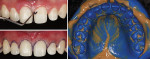

A sequence of extra- and intraoral photographs was taken. Frontal and lateral profile extraoral photographs of the patient's face were taken at different moments, including images while her lips were sealed and slightly opened, and a discreet smile and a wide smile (Figure 1). Closer views of the patient's mouth, including sealed lips, opened lips, and a wide smile, are shown in Figure 2. Figure 3 shows intraoral images of the maxillary arch and the dentition inmaximum intercuspation.

Preliminary full impressionsof the maxillary and mandibular arches were taken with polyvinyl siloxane (PVS) (Virtual, Ivoclar Vivadent, ivoclarvivadent.com). Based on the photographs and casts, a diagnostic wax-up was built to alter the patient's smile. Three important factors to evaluate in this step are the insertion pathway of the veneer, tooth substrate color, and the final color of the restoration.